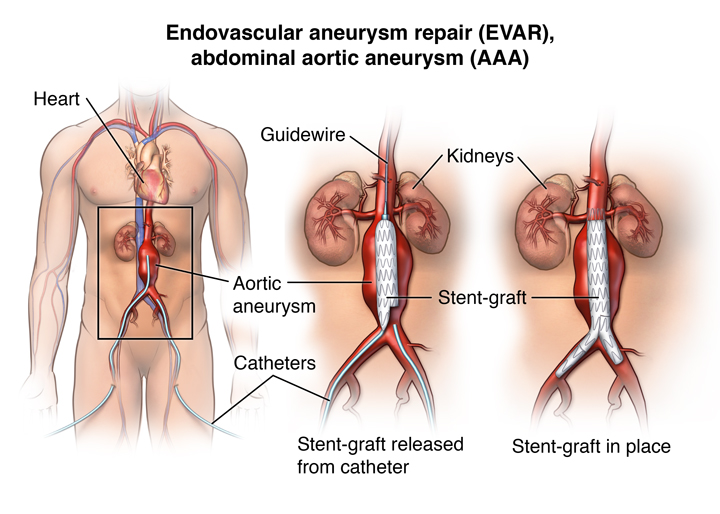

Aortic Aneurysm Abdominal

https://lookformedical.com/img/a/ab/RupturedAAA.png